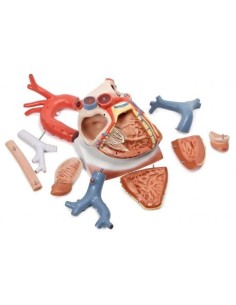

Des modèles anatomiques détaillés pour tous les besoins

Du crâne en 22 parties à verrouillage magnétique aux modèles de colonne vertébrale, des modèles d'articulation aux modèles de cœur, chaque pièce de notre collection est conçue pour une immersion totale dans l'étude de l'anatomie humaine. Nos modèles, réalisés à partir de scans d'os réels, garantissent une expérience tactile authentique et une fidélité de poids presque identique aux originaux.

Indispensables aux étudiants comme aux professionnels, nos modèles anatomiques sont des outils pédagogiques qui permettent d'observer les structures anatomiques avec précision, en évitant les dissections ou les études invasives. Ils sont également utiles pour expliquer les pathologies aux patients, ce qui rend la communication plus efficace et permet de gagner un temps précieux.